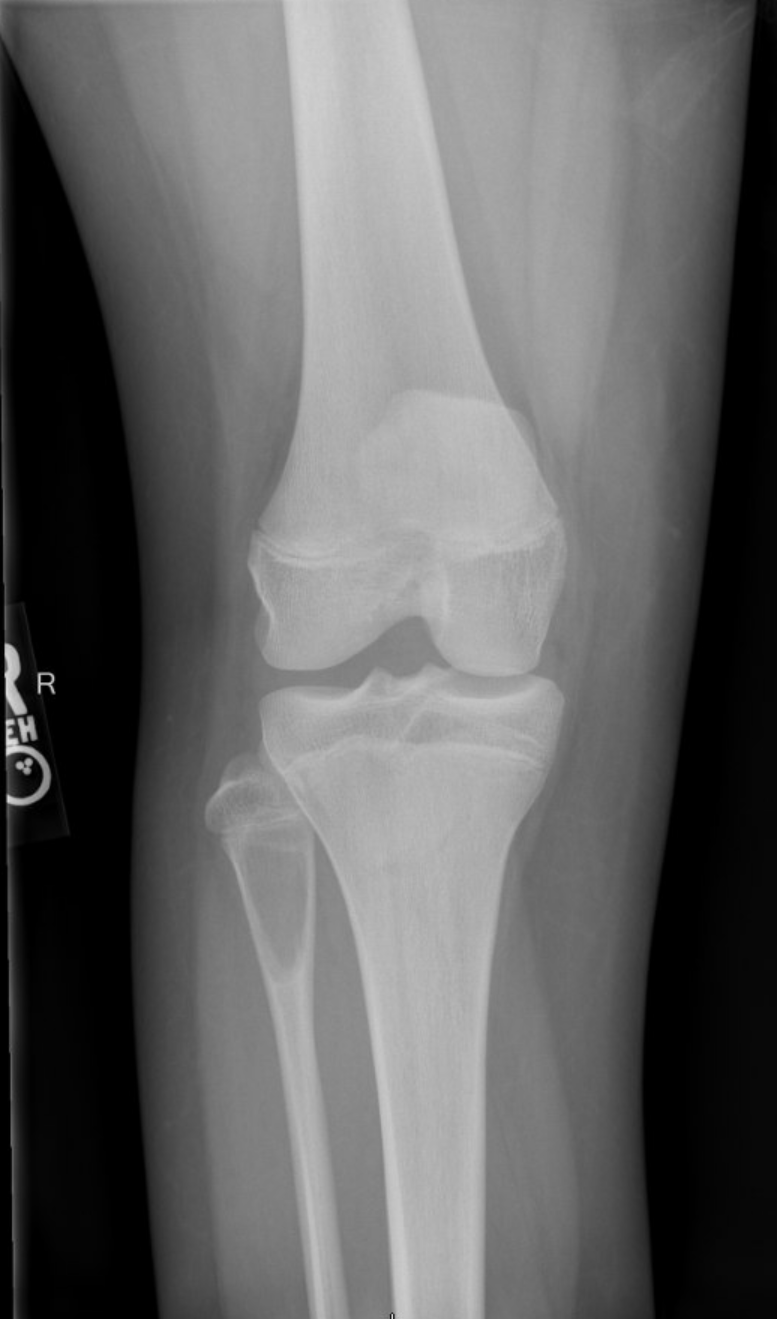

Aneurysmal Bone Cyst Orthogate

From www.orthogate.org

Aneurysmal Bone Cyst Orthogate Aneurysmal Bone Cyst Radiology Dental Bleeding may occur during an operation or biopsy for abc, as this cyst is an aneurys with numerous. Aneurysmal bone cyst (abc) is rare benign lesions of bone which are infrequent in craniofacial skeleton. Abc’s are characterized by rapid growth pattern. Areas similar to abcs are. Aneurysmal bone cysts (abcs) are benign bone lesions that may arise de novo in. Aneurysmal Bone Cyst Radiology Dental.